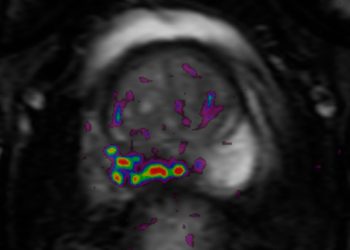

La resonancia magnética ha tomado un papel fundamental en el diagnóstico del cáncer de próstata, ya que nos permite confirmar o descartar la presencia de lesiones sospechosas en la próstata, disminuyendo así la cantidad de biopsias innecesarias y en los casos en que sea necesaria la biopsia aumenta su precisión diagnóstica. Cuando se confirma el diagnóstico de cáncer la resonancia también es de gran utilidad, ya que permite valorar la extensión de la enfermedad.

El diagnóstico definitivo de cáncer de próstata se obtiene mediante el analisis histopatológico del tejido extraído en una biopsia. La biopsia transrectal guiada por ultrasonido, técnica ampliamente utilizada desde la década de los 80`s es la mas conocida, sin embargo en la última década se han desarrollado nuevas técnicas con el objetivo de aumentar su precisión diagnóstica, una de estas es la biopsia prostática con fusión resonancia magnética-ultrasonido (MRI-TRUS) que permite sincronizar las imágenes obtenidas por resonancia magnética con las imágenes generadas por ultrasonido en tiempo real y dirigir la toma de muestras hacia las zonas de sospecha.